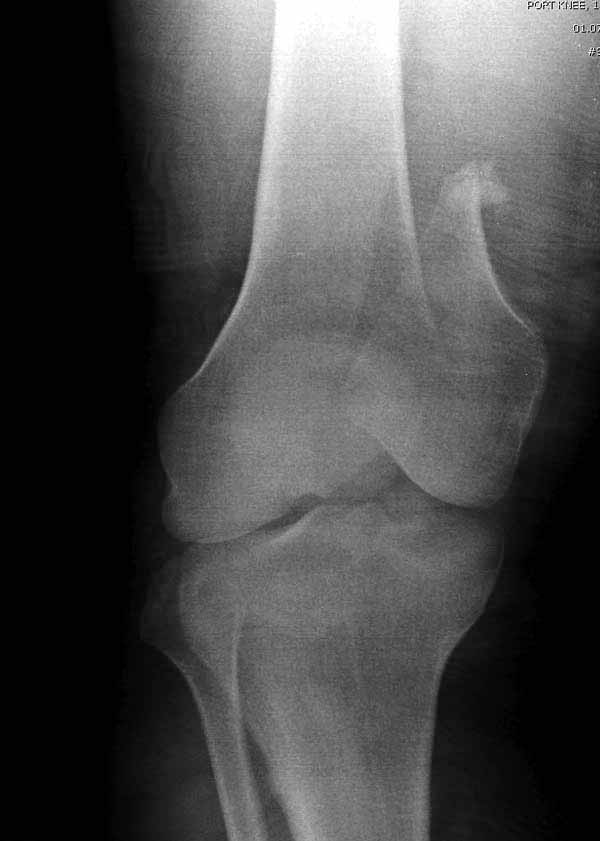

И не обратите, коллега, пока не сделаете четкие анфасные снимки (лучше с дистракцией) где будет четко визуализироваться малоберцовая кость. Думается, что и КТ здесь будет уместно, дабы не пропустить возможное флексионное повреждение (перелом Hoffa).

>Сразу не обратил ваше внимание именно на это, что сломаны оба мыщелка, и больший является именно медиальным мыщелком

А теперь по поводу лечения перелома. Среди всех чрез/меж-мыщелковых переломов в 38% сопровождются переломом в корональной плоскости, т.е перелом Hoffa. Nork et al, J Orthop Trauma, 87:564, 2005.

У больных как в этом случае, с вовлечением двух мыщелков правильно, что сделали вытяжение до операции. Здесь имеется флексионный компонент на другой стороне, и я бы рекомендовал операцию делать из двух доступов. Сперва фиксировать медиальную колонну custom made пластиной, обычно 1/3 тубулярной пластиной в 4.5 мм, потому что пока производители опаздывают с медиальной пластиной.